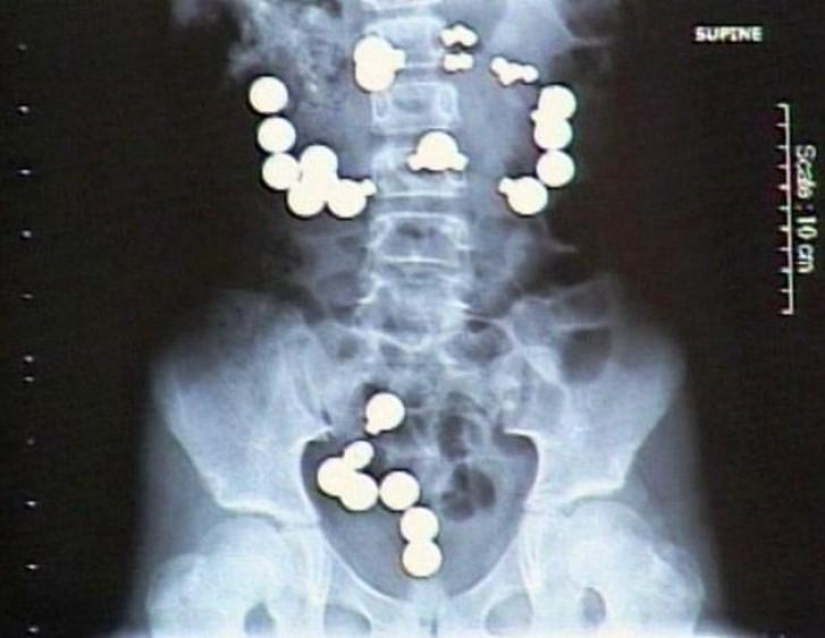

11. Ranas vivas.